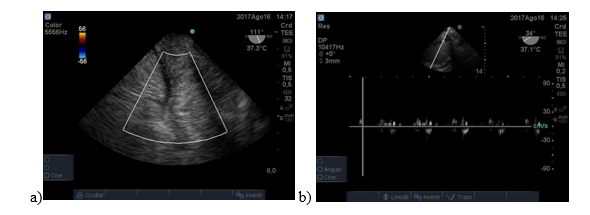

La cirugía se desarrolla sin incidentes y luego del desclampeo se produce hipotensión severa y paro cardíaco. Se coloca ETE que no muestra signos de enfermedad cardíaca, el ventrículo derecho era normal y los vasos hepáticos tenían adecuada perfusión. Figura 5. Se obtienen resultados de laboratorio que muestran severa e hiperkalemia (K plasmático de 7 mEq/L). Se inicia tratamiento con bicarbonato y cloruro de calcio.

Paciente de 66 años con diagnóstico de cirrosis por hepatitis C y hepatocarcinoma asociado y tratado con embolización 3 meses antes. Post desclampeo presenta descompensación hemodinámica y sangrado. A través de la ETE se fue guiando la reposición de volumen y el estudio del hígado demostró defectos severos en la perfusión hepática.Figura 6: a y b